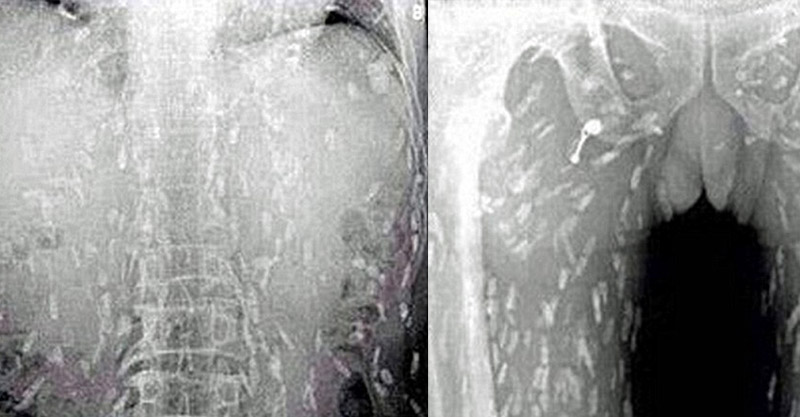

對很多人來說,生魚片是讓人欲罷不能的美食,但一名中國男子對生魚片的愛好卻差點要了他的命。據報導,一名男子因為腹痛跟皮膚癢前去就診,醫生幫他照X光時卻拍下駭人畫面。

原來男子的體內已經滿滿都是絛蟲寄生,看了讓人頭皮發麻。醫生認為他是因為吃了太多生魚片,才會有如此嚴重的感染。後來男子也轉往廣州市第八人民醫院接受治療。